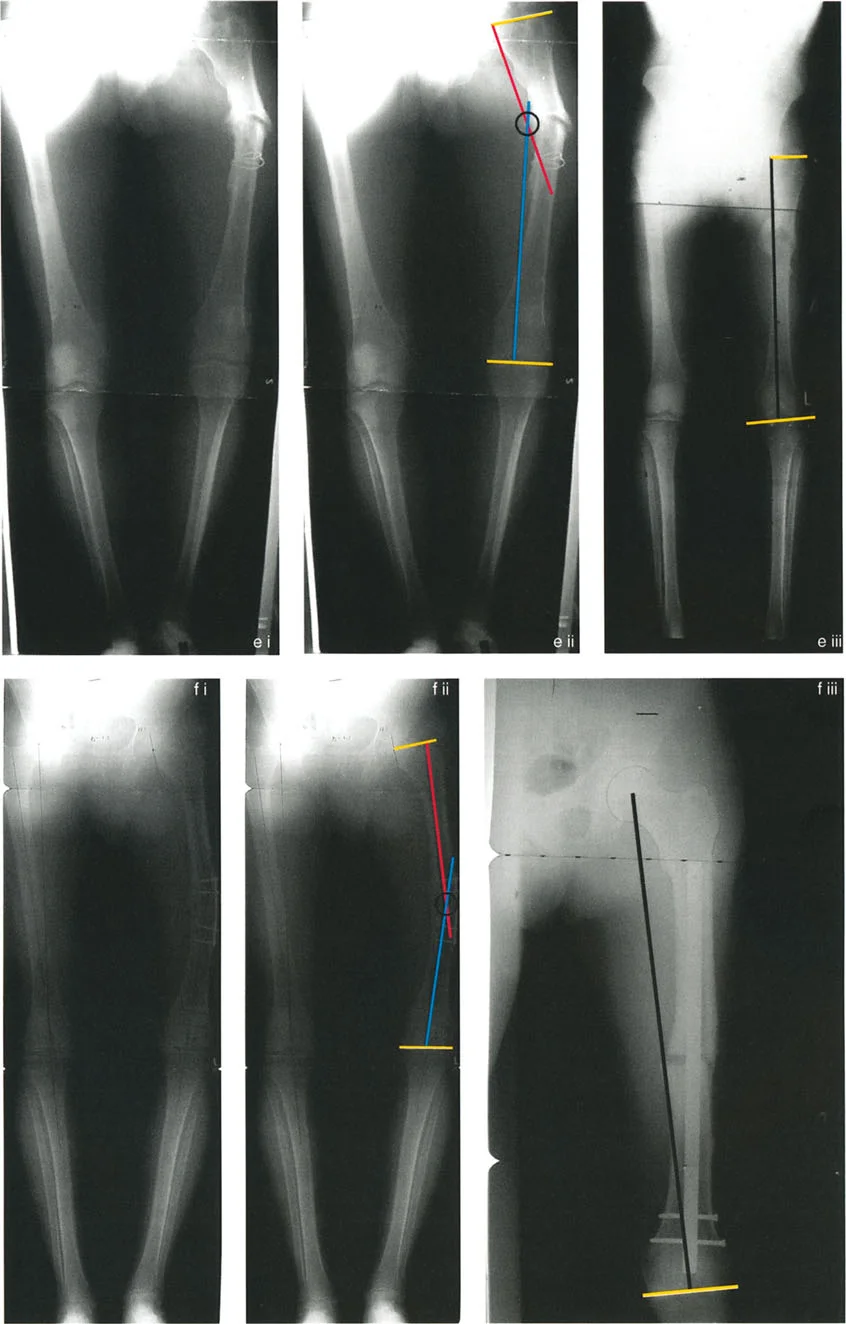

تحليل سيناريوهات العلاج: تشوه الفخذ الوحشي القريب من المفصل

دعونا نفحص سيناريو سريريًا كلاسيكيًا: تشوه الفخذ الوحشي (Valgus) البعيد.

تشوه عند مستوى مفصل الركبة (10 درجات تقوس للخارج)

تخيل تشوهًا وحشيًا في الفخذ البعيد بمقدار 10 درجات حيث يقع مركز دوران الانحراف (CORA) بالضبط عند خط مفصل الركبة.

* المشكلة: لا يمكننا استخدام قاعدة بضع العظم 1. فالقطع عبر مركز دوران الانحراف يعني القطع عبر غضروف مفصل الركبة، وهو أمر مدمر وممنوع.

* الحل (القاعدة 2): يجب علينا إجراء بضع العظم أقرب إلى مركز دوران الانحراف (في كردوس الفخذ البعيد). نضع محور تصحيح الانحراف (ACA) بالضبط عند مركز دوران الانحراف (خط المفصل).

* التنفيذ: نقوم بتصحيح زاوي بمقدار 10 درجات. نظرًا لأن بضع العظم أقرب إلى محور تصحيح الانحراف، فإن الجزء البعيد سينزاح إنسيًا (داخليًا). يتم استعادة المحور الميكانيكي بشكل مثالي، ويتم التخلص من انحراف المحور الميكانيكي (MAD)، ويكون توجيه مفصل الورك/الركبة طبيعيًا. النتيجة الوحيدة هي انزياح إنسي طفيف للمحور التشريحي (نتوء في الكردوس)، والذي يتغير شكله بمرور الوقت أو يكون غير مهم سريريًا. هذا يوضح خبرة الأستاذ الدكتور محمد هطيف في تحقيق أفضل النتائج مع أقل الآثار الجانبية.

تشوه عند مستوى صفيحة النمو البعيدة (33 درجة تقوس للخارج)

لننظر إلى تشوه وحشي أكثر شدة بمقدار 33 درجة حيث يقع مركز دوران الانحراف (CORA) عند مستوى صفيحة النمو البعيدة (شائع في توقف النمو بعد الصدمة لدى الأطفال).

* تطبيق القاعدة 1 (الأطفال): في الطفل، يمكن أحيانًا إجراء بضع العظم عبر صفيحة النمو (chondrodiatasis) أو بجوارها مباشرة. إذا كان القطع ومحور تصحيح الانحراف عند مركز دوران الانحراف، فإن تصحيح فتح الوتد بمقدار 33 درجة ينتج عنه محور تشريحي طبيعي، ولا يوجد انحراف ميكانيكي، ولا انزياح.

* تطبيق القاعدة 2 (البالغون): في البالغين، قد يكون القطع عند ندبة صفيحة النمو القديمة قريبًا جدًا من المفصل لتثبيت مستقر. إذا تم نقل بضع العظم أقرب، ولكن ظل محور تصحيح الانحراف عند مركز دوران الانحراف، فإن تصحيح 33 درجة سيؤدي إلى الانزياح المطلوب لإعادة محاذاة الطرف بشكل مثالي.

* خطر سوء وضع محور تصحيح الانحراف: إذا وضع الجراح محور تصحيح الانحراف عند مستوى بضع العظم الأقرب (متجاهلاً مركز دوران الانحراف)، فإن تصحيح 33 درجة سيترك انحرافًا ميكانيكيًا إنسيًا متبقيًا. لإصلاح هذا الانحراف، قد يميل الجراح إلى الإفراط في التصحيح إلى 36 درجة. بينما يؤدي هذا إلى استقامة الساق، فإنه يسبب سوء توجيه تقوسي (Varus) لمفاصل الورك والركبة، مما يؤدي إلى التهاب المفاصل المبكر. هذا هو بالضبط ما يسعى الأستاذ الدكتور محمد هطيف إلى تجنبه من خلال التخطيط الدقيق.